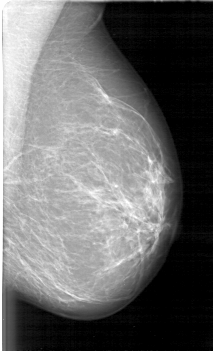

D_4090_1.LEFT_CC

LEFT_CC LINES 5371 PIXELS_PER_LINE 3361 BITS_PER_PIXEL 12 RESOLUTION 43.5 NON_OVERLAY